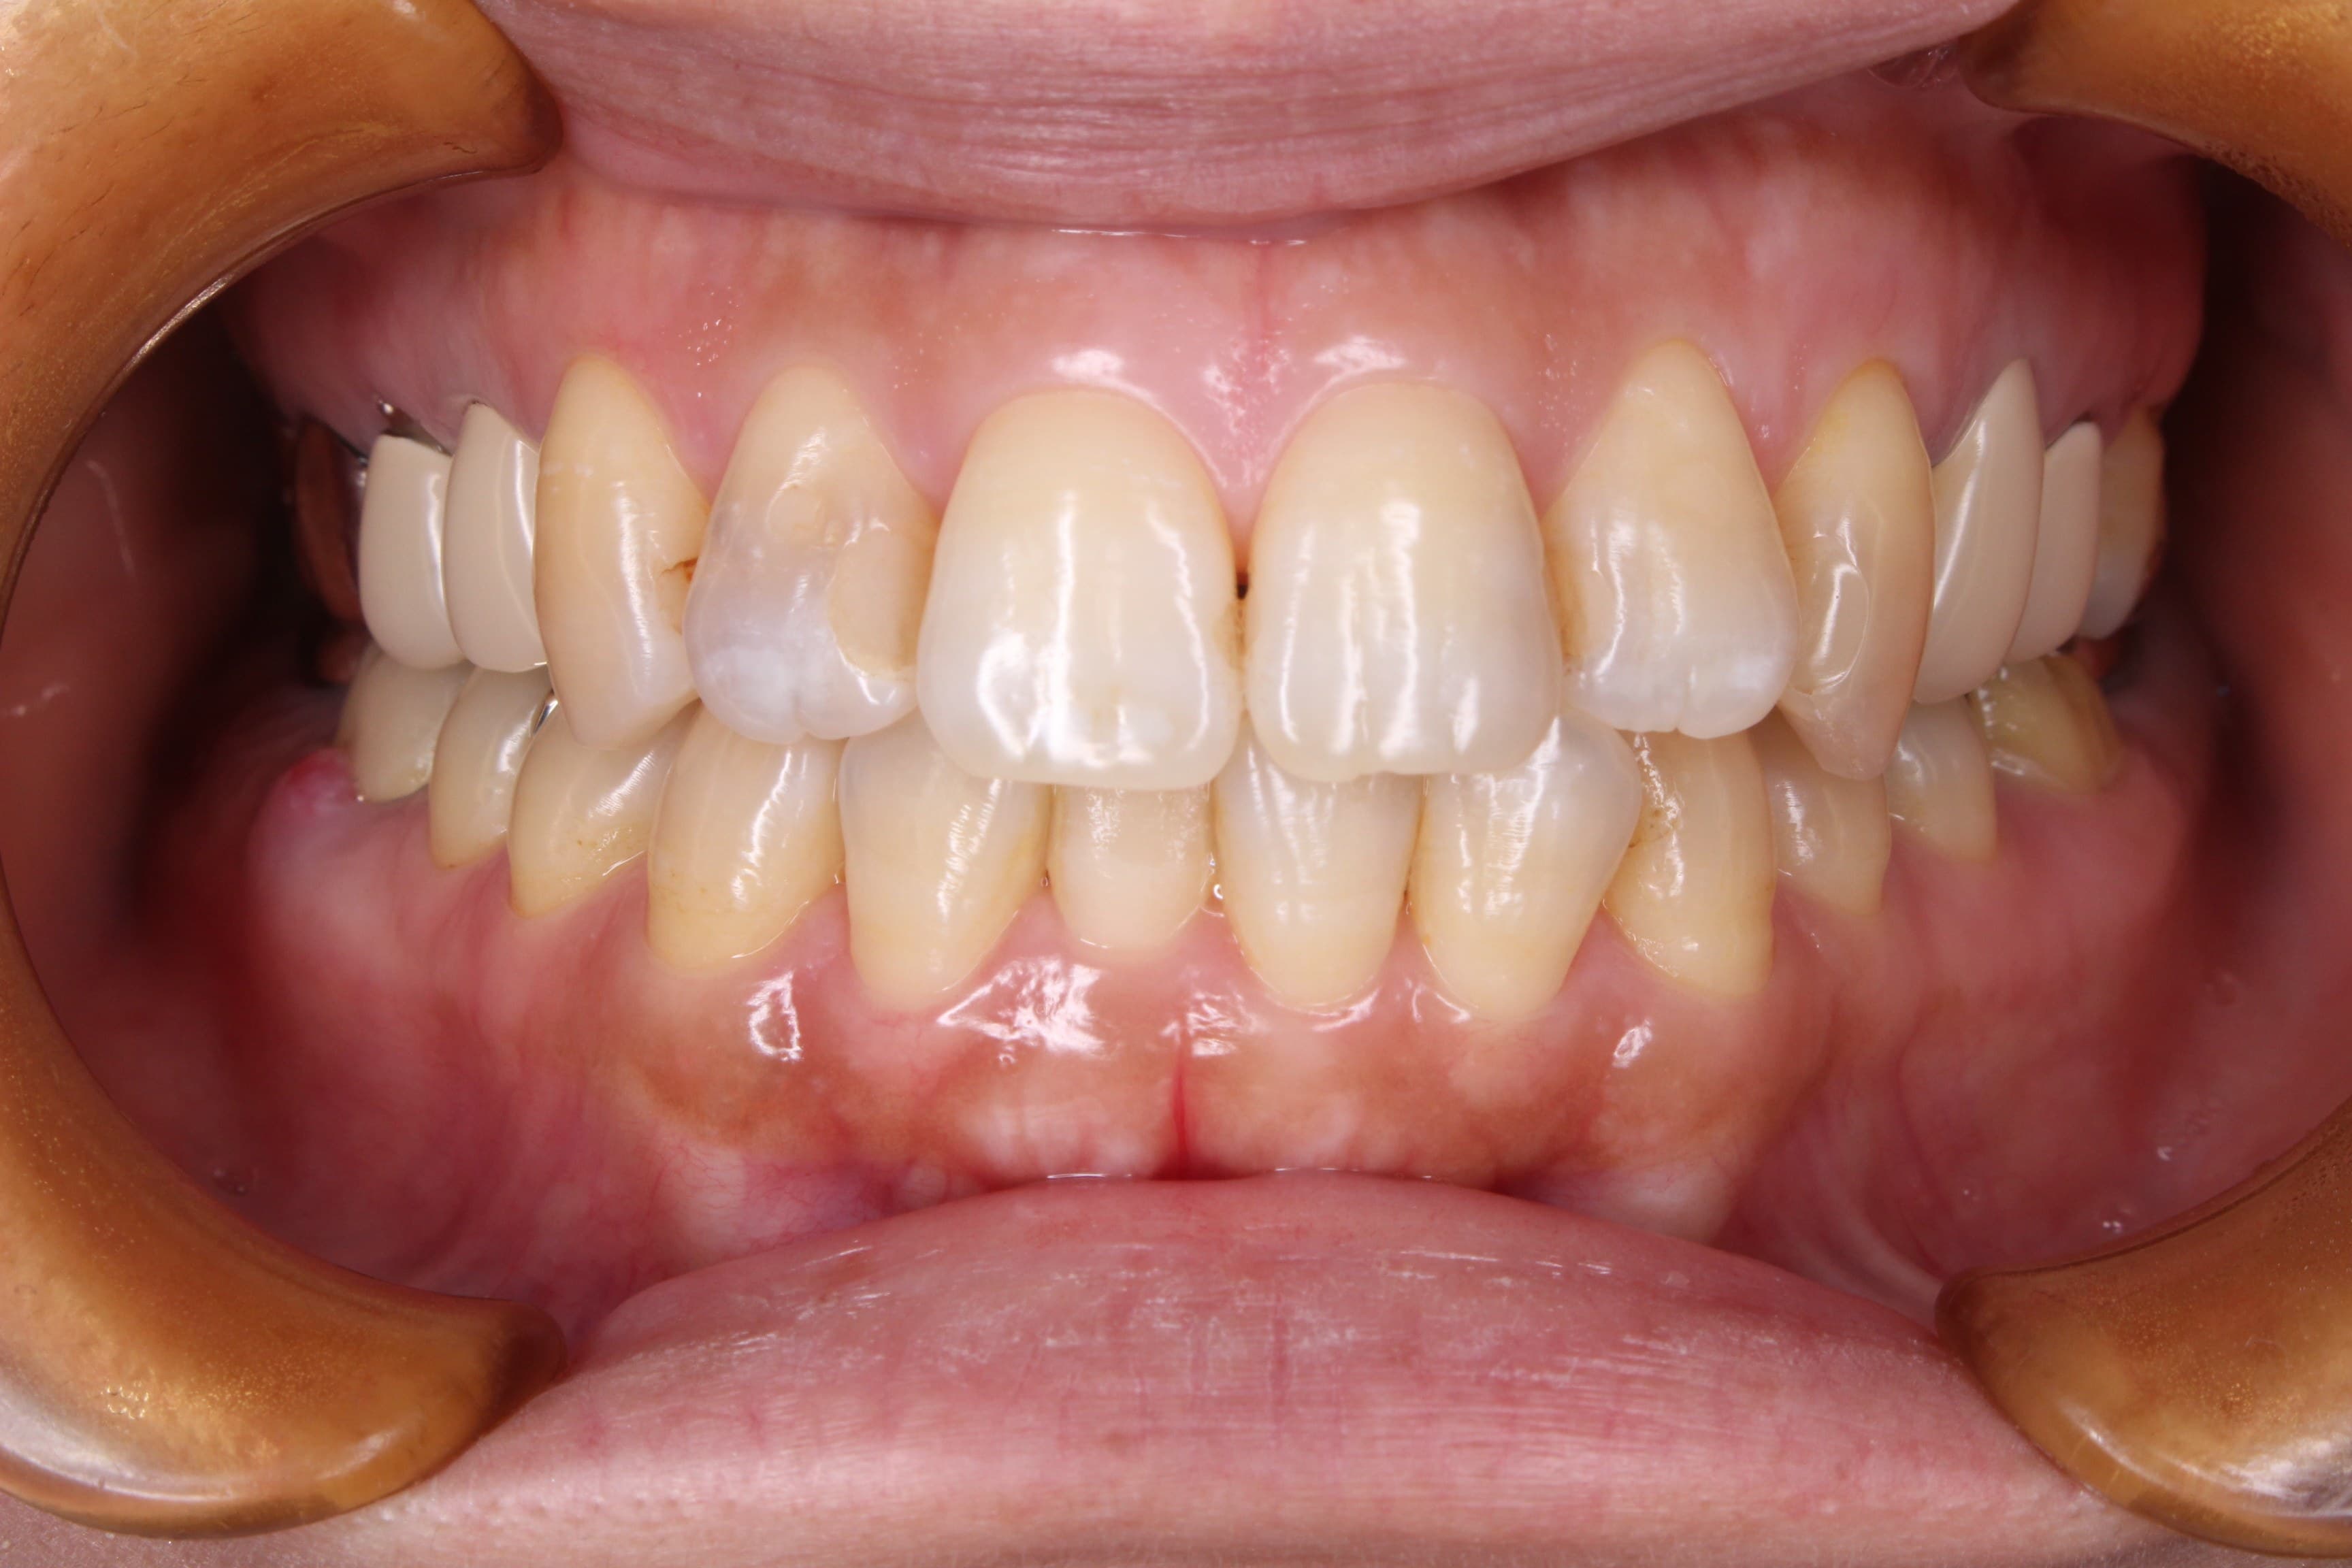

(治療前)

育児と家事と仕事に追われて、左下が5年前から腫れを繰り返しており、我慢できない程痛くなった時に別の歯科医院を受診したところ、抜歯の診断を受けたとのことでした。

今回も実際に歯周病菌にも感染しており、ご自身でも自覚があった為、歯周病の原因と治療法についてお伝えし歯周専門治療を行うこととしました。